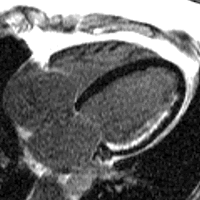

A 4 chamber view of the heart using SSFP cine imaging. Compare the image orientation (4 chamber) with the short axis view of the movie above